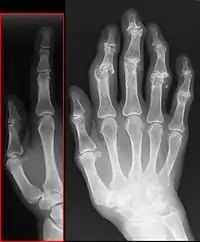

Radiologie

La radiographie standard, sans préparation, est suffisante au diagnostic de la maladie arthrosique.

Quatre signes radiologiques sont caractéristiques :

- le pincement de l'articulation par destruction du cartilage (diminution de l'épaisseur du cartilage) ;

- une condensation osseuse sous le cartilage ;

- la présence d'excroissances osseuses ou ostéophytes ;

- la présence de géodes (trous à l'emporte-pièce) dans l'os autour de l'articulation.

Il n'y a pas de parallélisme entre l'importance des signes radiographiques et les symptômes ressentis : une arthrose importante sur la radiographie peut rester asymptomatique. Inversement, une arthrose très douloureuse peut ne présenter que de modestes altérations radiologiques.